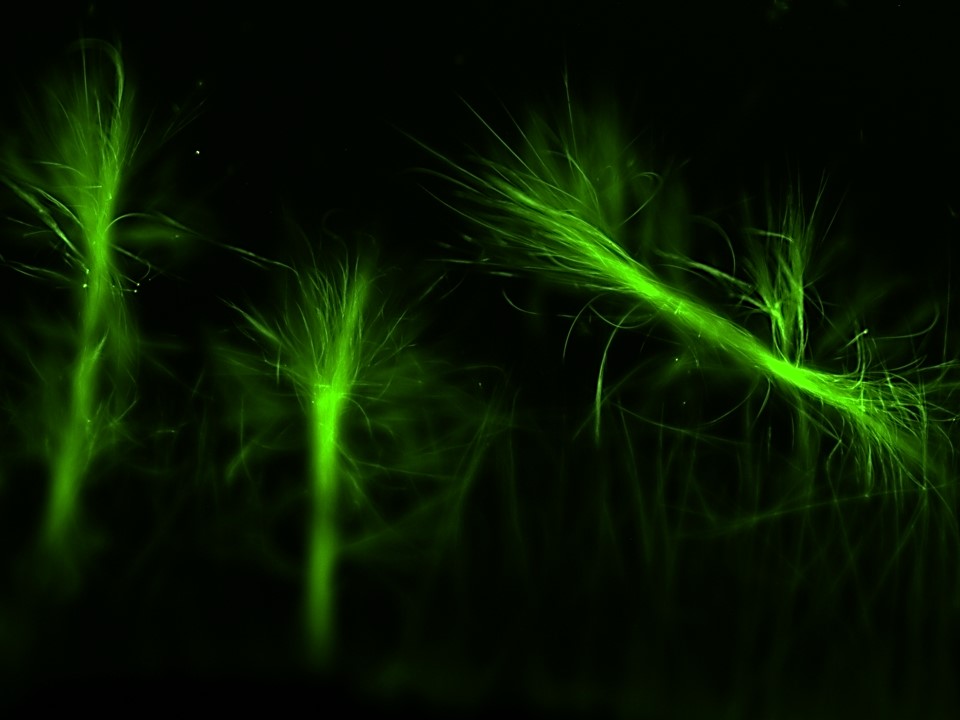

Aggregation of proteins and peptides into toxic amyloid structures is a critical biological event that leads to the onset of several pathological conditions including Alzheimer’s disease, Huntington’s disease, Parkinson’s disease, etc. This decade has observed an upsurge in the prevalence of more than 50 amyloidogenic diseases. We will be working to gain a mechanistic understanding of the protein aggregation process, including its structural insights, and apply this fundamental knowledge to study the molecular events in protein aggregation and its pathology in neurodegenerative diseases.